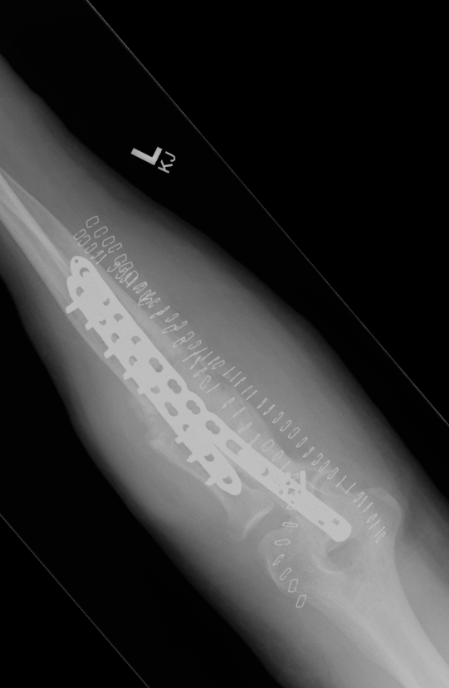

ORIF with plates

Intramedullary fixation

ORIF with DCP plates

Fixation with DCP plates

Revision compression plating + drill intra-medullary canals + autograft

Masquelet induced membrane technique - defects up to 5 cm

Vascularized fibular bone graft - defects > 5 cm

Masquelet

- 32 infected forearm nonunions

- first stage: removal hardware / antibiotic cement for 6 weeks

- second stage: cancellous bone graft + plate

- 100% union rate